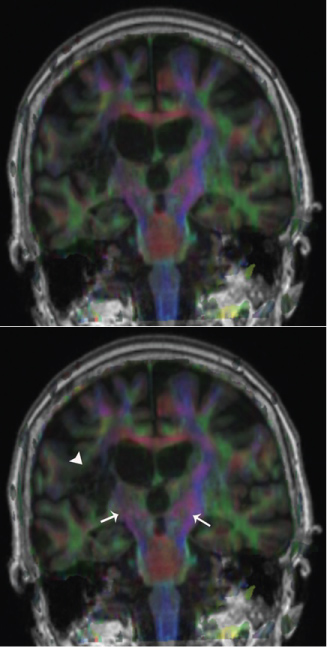

Three subjects were excluded after the full initial scan due to poor imaging quality (movement artifacts or inability to complete the imaging protocol). Seven subjects were included and were studied before and after the injections. The obtained images were post processed in an independent workstation using Syngo Via® software to image the corticospinal tracts of the affected and contralateral sides (Figure 1 and Figure 2), the corpus callosum (Figure 3) and the tracts in the white matter of the frontal, parietal, temporal and occipital lobes of the affected and contralateral sides. The seeding points for tractography [21] were placed in the rostral cerebral peduncles on axial plane for the corticospinal tracts, in the corpus callosum on the sagittal plane, and in the white matter of the cerebral lobes within the boundaries set by the Talairach Atlas on axial plane. Fractional anisotropy values were obtained for each of the tracts. Each measurement was repeated three times to ensure consistency.

Figure 1: FA maps fused to coronal T1 sectioning rostrally the cerebral peduncles showing CSTs in blue (white arrows). Note the lesion (white arrowhead) on the affected side on the patient's right (left side of the image) and how it extends to the right CST. View Figure 1